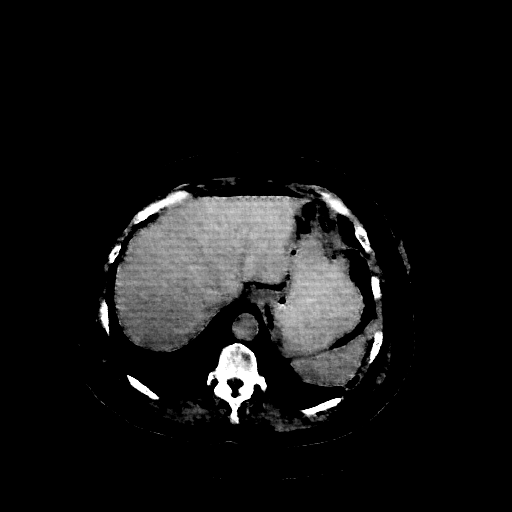

Reconstructed NATIVE CT scan (cycle consistency)

Full window (WL 1023.5, WW 4095 β†’ Low βˆ’1024, High +3071)

Lung window (WL -600, WW 1500 β†’ Low βˆ’1350, High +150)

Mediastinum window (WL 40, WW 400 β†’ Low βˆ’160, High +240)